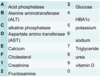

Which one is increased in a patient with Paget’s disease of the bone?

C) Alkaline phosphatase (ALP)

Which one is increased in a patient with osteomalacia?

C) Alkaline phosphatase

Which one is increased in a patient following an acute MI?

D) AST

Which one of the above is most increased in a patient with jaundice caused by a gallstone?

C) Alkaline phosphatase (OBSTRUCTIVE JAUNDICE)

Which one is most increased in a patient with jaundice caused by viral hepatitis?

ViraL = ALT (B)

Which one is most increased in a patient with jaundice caused by chronic alcoholic cirrhosis?

D) Aspartate amino transferase (AST)

Which one is most increased in a patient with prostatic carcinoma?

A) Acid phosphatase (we’ve now changed the name to prostate specific antigen/PSA)